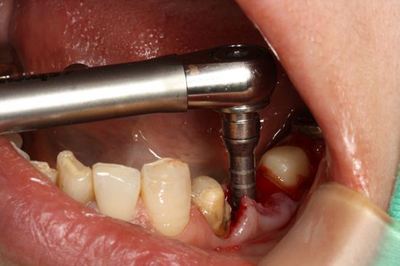

安全な深度までドリリングして深度ゲージで確認します。

ここからは粘膜を剥離して実際の歯槽骨を見ながらドリリングします。

ドリルのサイズをステップアップして最終サイズまで拡大しました。

インプラント埋入前にタップを切ります。